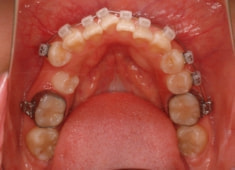

治療後(1年12ヶ月後)

治療開始から5ヶ月後